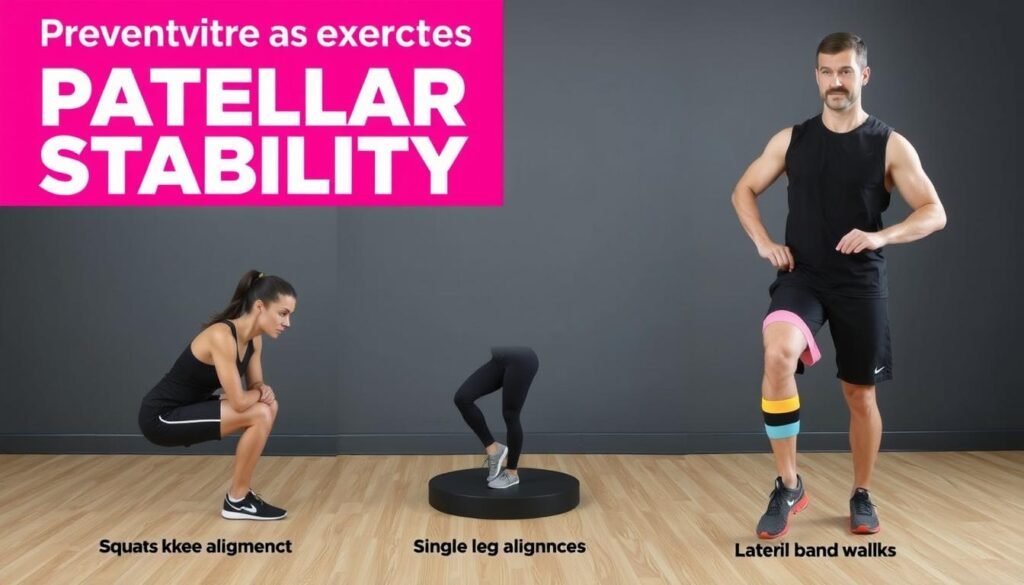

Präventionsmaßnahmen bei Patellaluxation

Präventive Übungen zur Stärkung der stabilisierenden Muskulatur und Verbesserung der Kniestabilität

Nach einer Patellaluxation oder bei erhöhtem Risiko sind präventive Maßnahmen besonders wichtig, um erneute Luxationen zu vermeiden und die Kniestabilität zu verbessern.

Übungen für die Oberschenkelmuskulatur

Eine kräftige und ausgewogene Oberschenkelmuskulatur ist der beste Schutz gegen Patellaluxationen:

Kräftigungsübungen

- Beinstrecken: Gezieltes Training des M. vastus medialis

- Kniebeugen: Mit korrekter Beinachse (Knie nicht nach innen)

- Einbeinstand: Verbessert Koordination und Stabilität

- Seitliches Beinheben: Stärkt die Hüftabduktoren